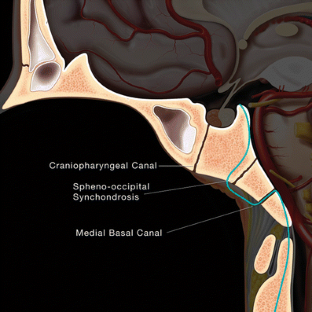

Fig. 1